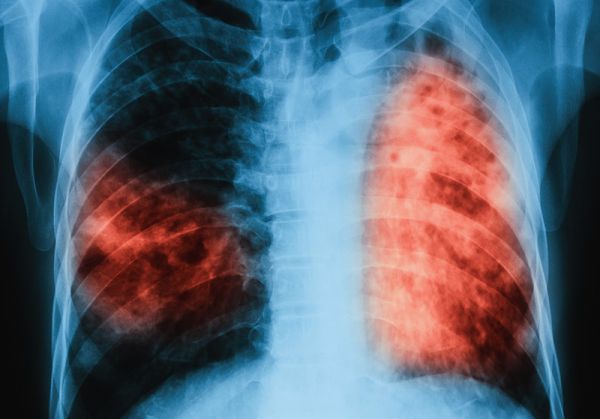

Новата наредба детайлизира процесите и всички изисквания към извършваните дейности по диагностика, изследване, регистриране и съобщаване по електронен път на случаите на туберкулоза. „Това ще осигури устойчивост на постигнатите резултати в контрола на туберкулозата в страната след спиране на финансирането от Глобалния фонд за борба срещу СПИН, туберкулоза и малария“, пише в доклада на министъра към проекта.